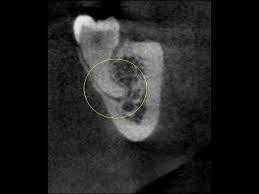

CT撮影できちんと診断

多くの歯科医院にあるデンタルレントゲンは、歯や顎の骨の状態を二次元的にのみ撮影できます。CTはそれに対して、三次元的な撮影が可能です。当院では立体的に診断できるCTを用いて歯の位置を正確に分析します。歯の根の先端と神経の位置関係をきちんと調べてから抜歯を行うので、写真のような歯の根と神経が近接している症例でも安心して治療を受けることが可能です。